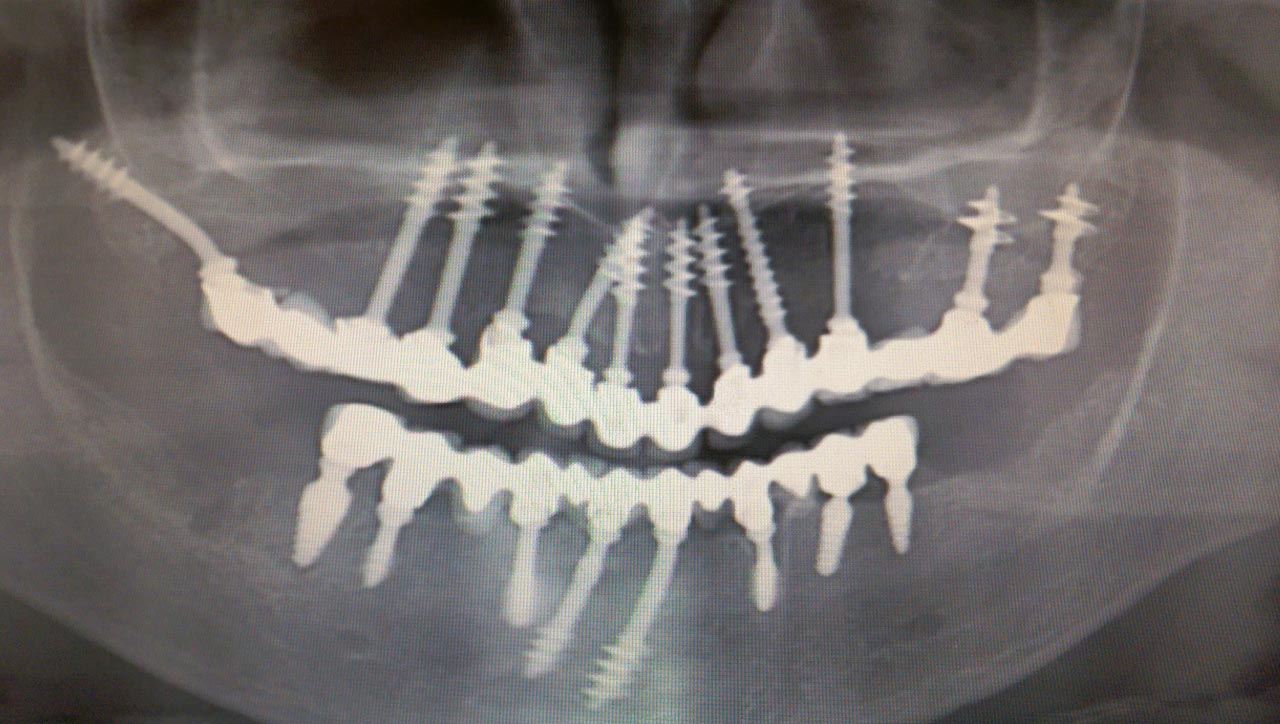

IHDE implantátumokkal

Amit az Ihde Azonnal Terhelhető Implantátum Rendszerről tudni érdemes

IHDE implantátum vagy hagyományos implantátum?

1-2 fog, vagy egy teljes állcsont?